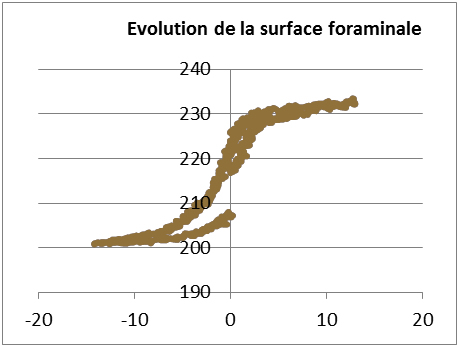

Evaluation de l’influence des implants inter épineux sur la cinématique du rachis (doctorat du Dr Fréderic Khiami)

Évaluation de l’influence des implants inter épineux sur la cinématique du rachis (doctorat du Dr Fréderic Khiami)